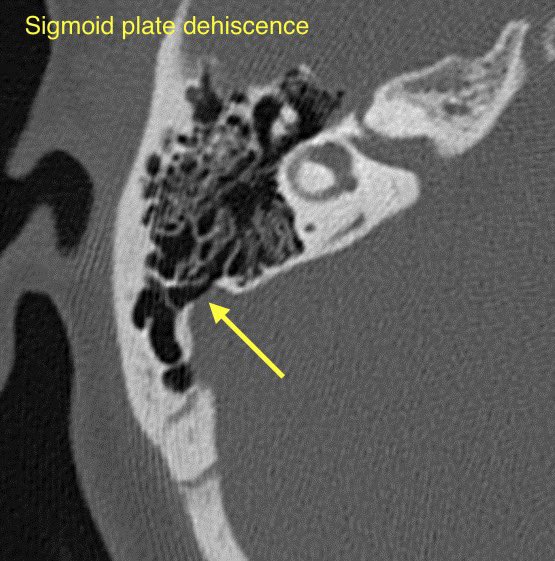

🔷SIGMOID SINUS WALL ANOMALIES

1️⃣Sigmoid plate dehiscence

🔹Sigmoid plate dehiscence: Thinning or absence of the normal cortical bone covering the sigmoid sinus resulting in direct contact of the venous sinus wall with mastoid air cells

💡 Sigmoid plate dehiscence w/ or w/o diverticulum is one of the most common imaging abnormalities at CT for pulsatile tinnitus (up to 40%). These findings are more prevalent in patients with TSS and IIH